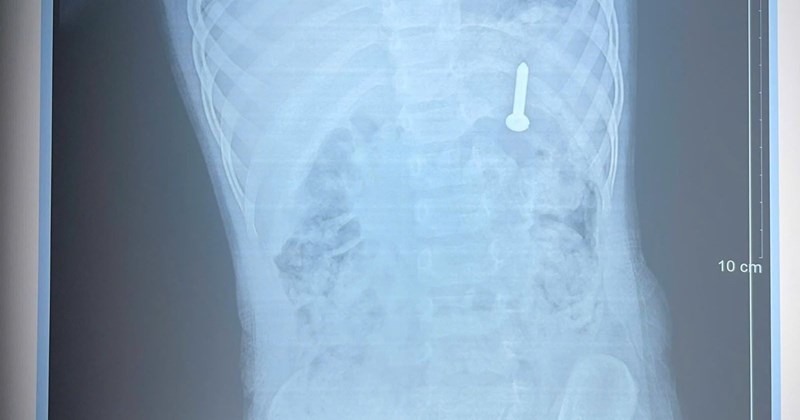

Một bé gái 11 tuổi ở Hà Nội đã phải chịu đựng tình trạng viêm âm đạo kéo dài suốt 5 tháng. Sau khi đến khám tại Bệnh viện Phụ sản Hà Nội, các bác sĩ đã phát hiện và gắp ra một dị vật hoen gỉ bên trong âm đạo của bé VnExpress. Sự việc này không chỉ gây ảnh hưởng đến sức khỏe mà còn gây ra những lo lắng cho gia đình và cộng đồng.

Gia đình cho biết, trẻ bị ra dịch vàng tại âm đạo suốt 5 tháng, đi khám nhiều cơ sở, được chẩn đoán viêm âm hộ và cho thuốc điều trị. Tuy nhiên, sau nhiều đợt dùng thuốc, tình trạng của bé không cải thiện. Ngày 20/3, tại Khoa Khám bệnh C1 – Bệnh viện Phụ Sản Hà Nội, bác sĩ Lê Thị Hiếu, Trưởng khoa K

Bé gái 11 tuổi đã phải trải qua thời gian dài khó chịu vì tình trạng viêm nhiễm. Gia đình đã đưa bé đến Bệnh viện Phụ sản Hà Nội để được thăm khám. Tại đây, các bác sĩ đã tiến hành kiểm tra và phát hiện dị vật lạ trong âm đạo của bé VnExpress. Ngay sau đó, các bác sĩ đã tiến hành gắp dị vật ra khỏi cơ thể bé.